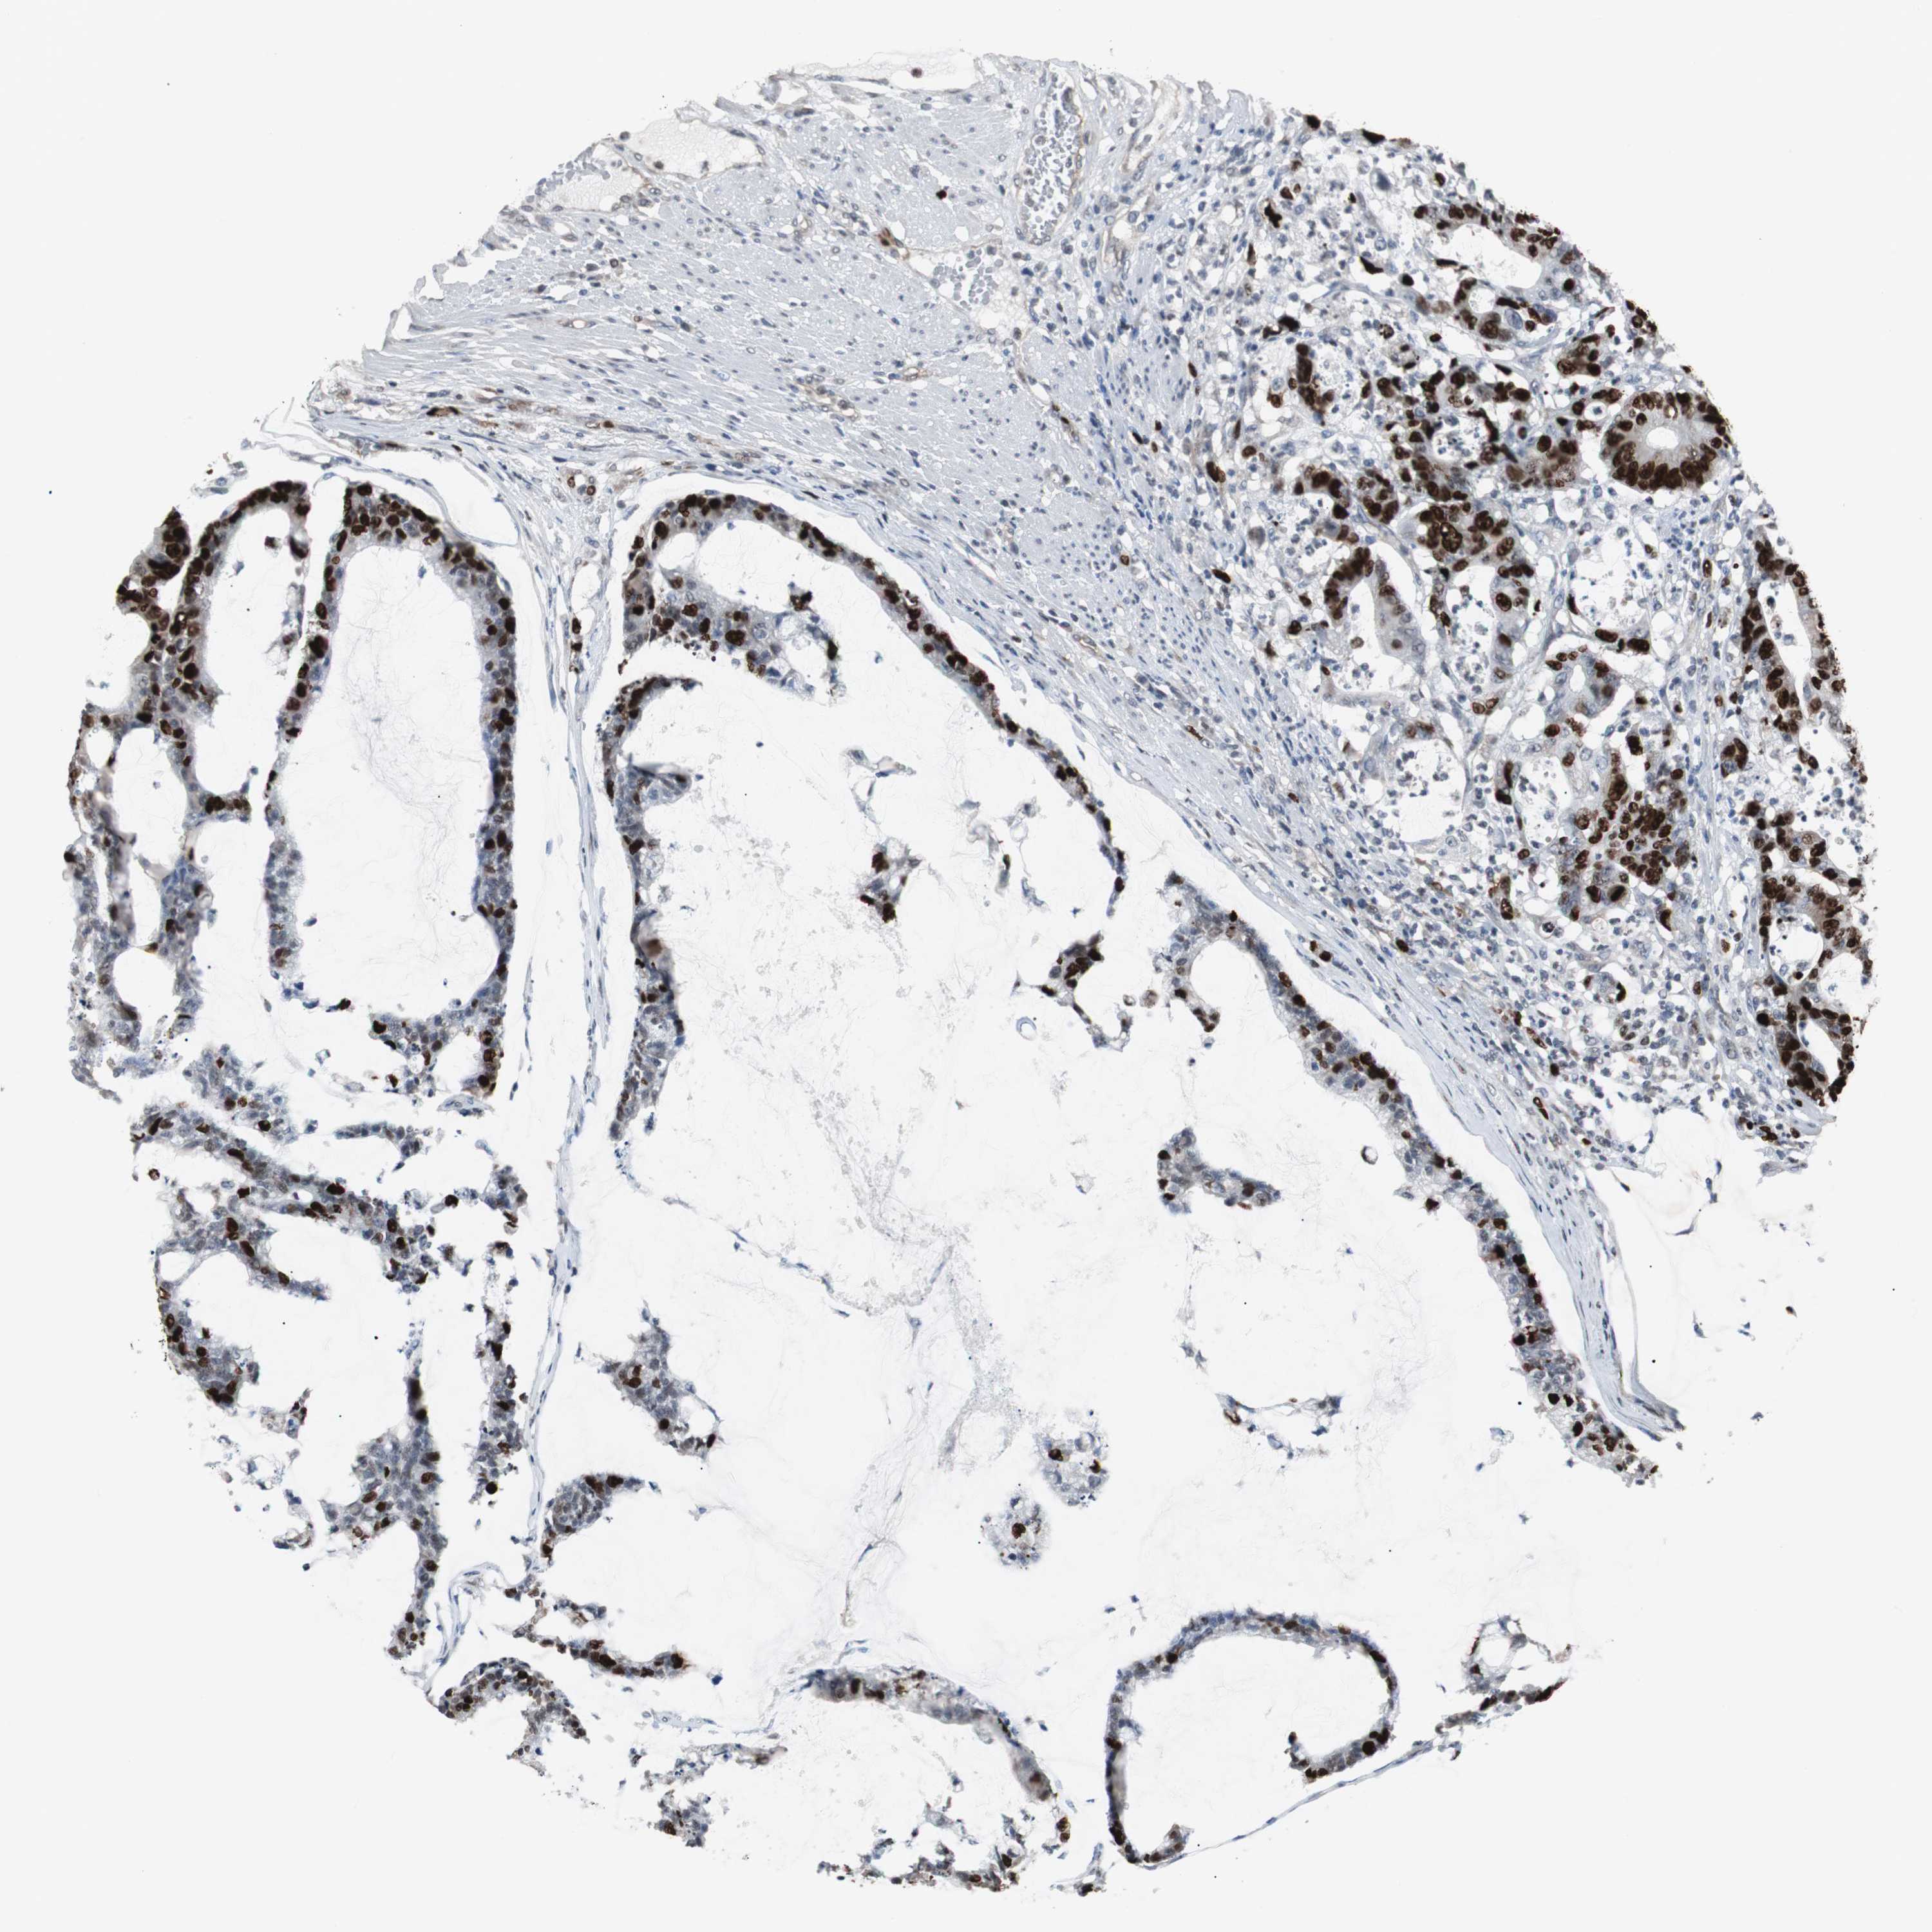

CANCER COLORECTAL CANCER Show tissue menu

Colorectal cancer

Human cancer

Colon adenocarcinoma